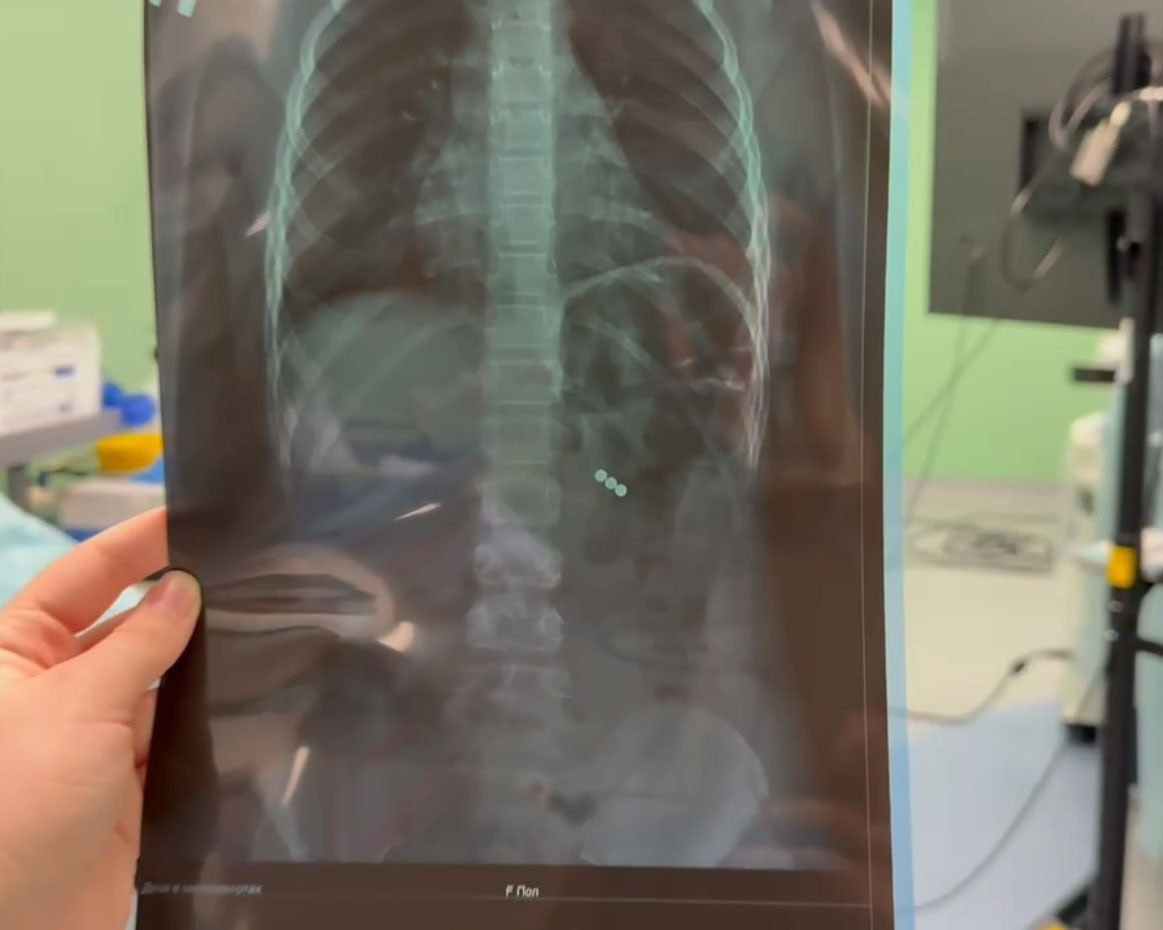

В Иркутскую областную детскую клиническую больницу поступила восьмилетняя девочка которая во время игры в школе случайно проглотила три магнитных шарика Ситуация была крайне опасной так как магниты притянулись друг к другу и вызвали перфорации в организме Иркутские хирурги выполнили экстренное малоинвазивное т е с минимальным проникновением в организм вмешательство и успешно удалили инородные предметы Девочка уже чувствует себя хорошо Об этом сообщил заслуженный врач России Юрий Козлов Сегодня самая большая проблема неодимовые магниты которые используются как компоненты детских игрушек Если проглатывание одиночного магнита не несет значительной угрозы для здоровья ребенка то проглатывание множественных магнитных инородных тел при притягивании их между собой оказывает силу до полукилограмма что может вызвать ишемию некроз и перфорацию стенок кишечника Родителям важно помнить что жизнь и здоровье детей находится в их руках отметил Юрий Козлов

Врачи спасли девочку проглотившую три магнита Об этом сообщил главный врач Иркутской областной детской клинической больницы Юрий Козлов По его словам девочка играла подбрасывая магниты и ловя их ртом в какой то момент три предмета оказались внутри Опасность заключалась в том что магниты притянулись друг к другу и вызвали перфорации внутренних тканей Медики провели экстренное малоинвазивное вмешательство и успешно извлекли инородные предметы Сейчас ребёнок чувствует себя хорошо угрозы жизни нет Юрий Козлов призвал родителей убрать магнитные игрушки которые могут представлять опасность для детей Doctor Yuraa Ircity теперь в MAX

Игра в школе едва не закончилась трагедией В Иркутской области 8 летняя девочка проглотила магниты Безобидные магнитные шарики которые продаются в каждом детском магазине едва не стали причиной настоящей трагедии В Иркутскую областную детскую больницу поступила 8 летняя девочка Во время игры в школе она случайно проглотила три маленьких магнитных шарика Ситуация была крайне опасной Магниты притянулись друг к другу и вызвали перфорации Вместе с командой мы выполнили экстренное малоинвазивное вмешательство и успешно удалили инородные предметы поделился главный врач Иркутской областной детской больницы Юрий Козлов Сейчас девочка идет на поправку но этот случай должен стать серьезным уроком для всех родителей Как отметил Юрий Козлов на сегодняшний день самой большой проблемой являются неодимовые магниты Они существуют разных форм и часто представлены в детских игрушках Если проглатывание одиночного магнита не несет значительной угрозы для здоровья ребенка то проглатывание множественных магнитных инородных тел при притягивании их между собой оказывает силу до полукилограмма поделился главный врач По словам медиков попадание таких сильных магнитов может легко привести к их соединению и вызвать ишемию некроз и другие серьезные заболевания